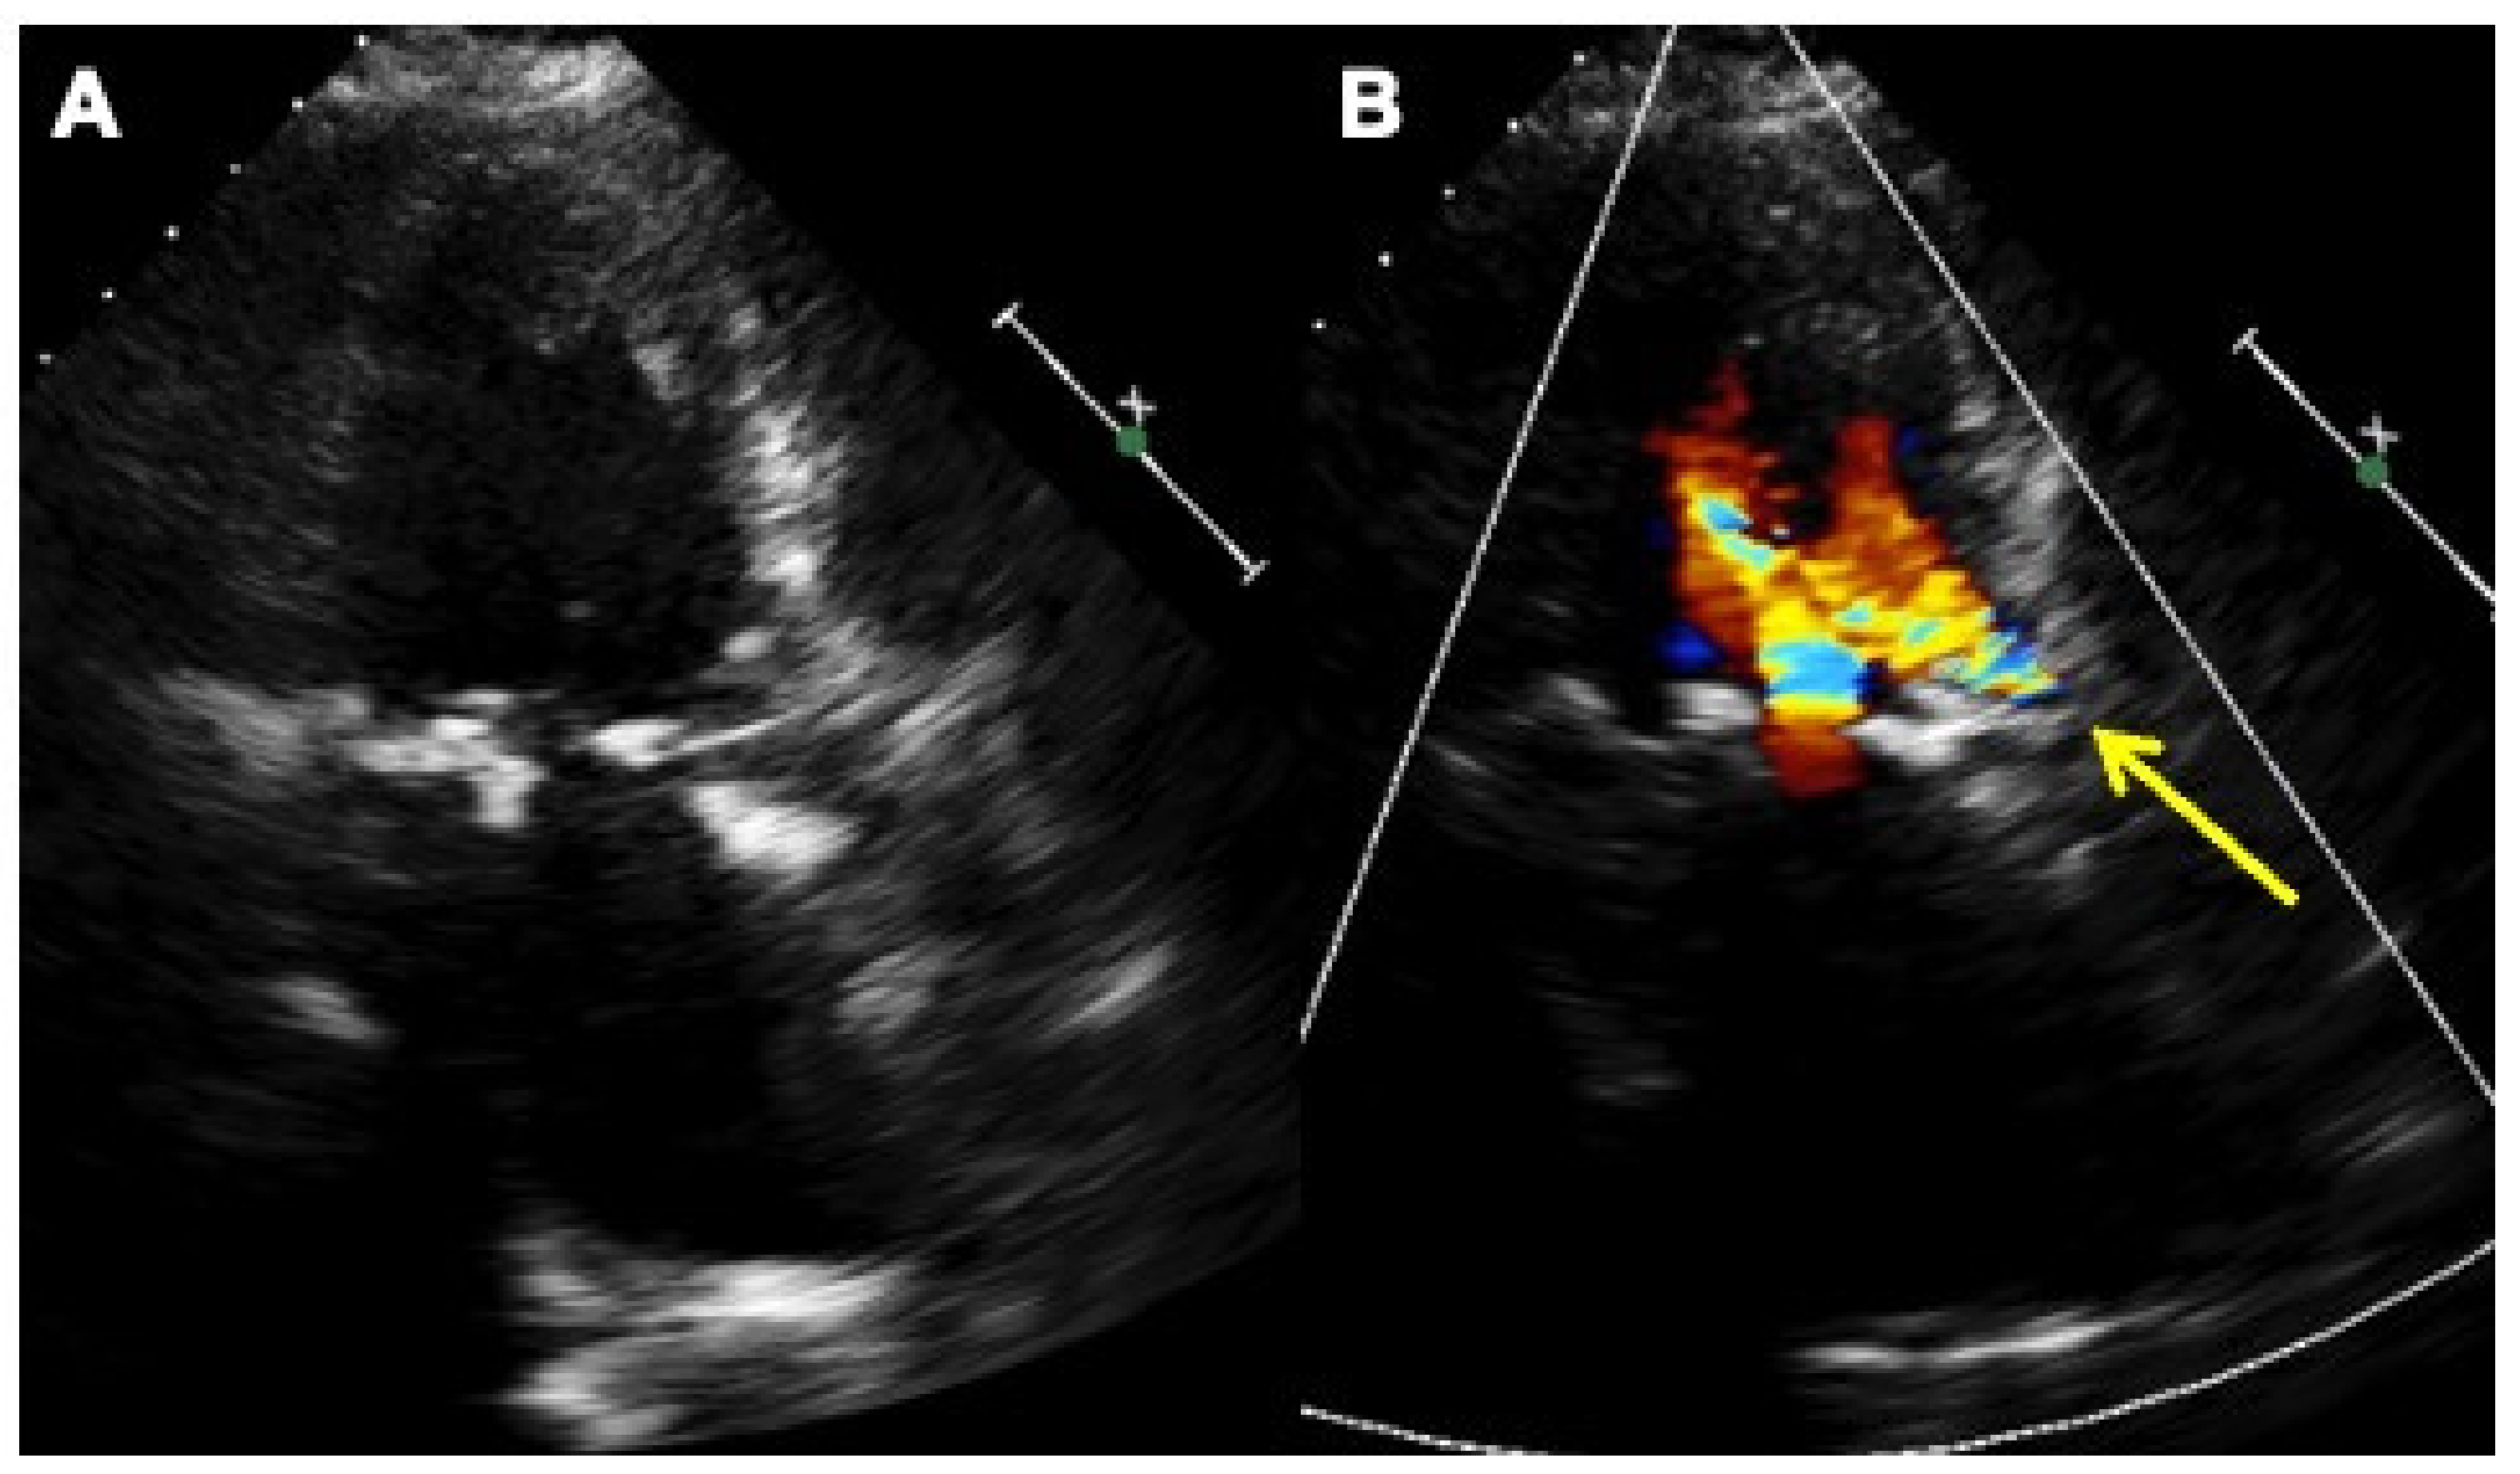

Two-dimensional transthoracic echocardiography color Doppler in two-chambers plane without (A) and with color Doppler (B) showing the self-expandable aortic biological valve in place, the paravalvular leak at the left coronary aortic cusp with the corresponding regurgitant jet (yellow arrow).

Figure 5.